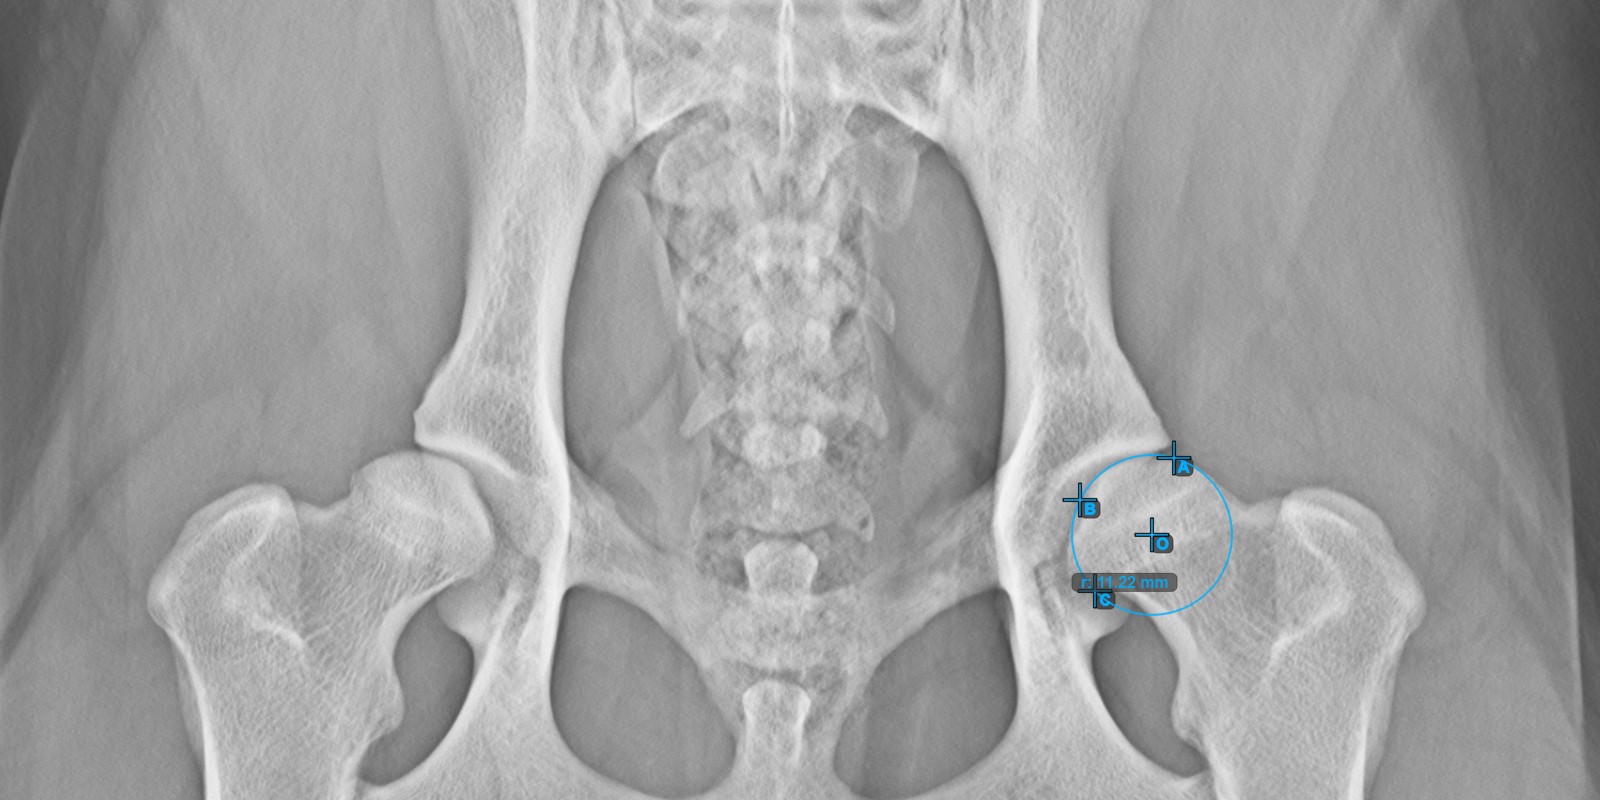

Continue by marking the three points on the articular surface of the right Caput Femoris.

Mark the three points on the articular surface of the right Caput Femoris (outside of the Fovea Capitilis). Regardless of the order, make sure to mark the most cranial point, the most caudal point and the midpoint of the femoral head. A circle will be automatically constructed based on the three placed points.

The image below depicts the typical placement of the three points on the articular surface of the right Caput Femoris.

../../_images/image100.jpg